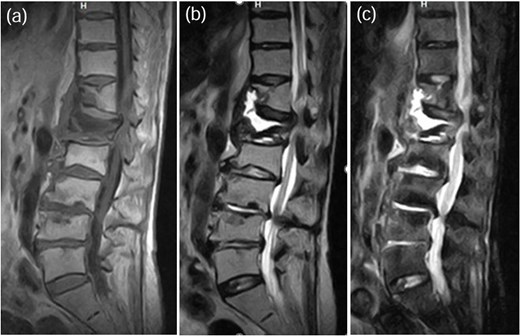

A 78-year-old woman was treated conservatively for an osteoporotic vertebral fracture at L1 with a rigid brace and osteoporosis medication. After 5 months of conservative treatment, her back pain persisted, and she subsequently developed lower limbs symptoms. She experienced severe thigh pain while standing. Plain radiographs showed an intervertebral cleft at L1 (Fig. 4), and a CT scan revealed osteolysis of the L1 vertebral body and the inferior endplate of Th12 (Fig. 5). MRI demonstrated high signal intensity changes in the L1 vertebral body and the anterior paravertebral area at L1-Th12 (Fig. 6). Blood tests showed a normal inflammatory response CRP: 0.28 mg/dL and WBC: 3.7 × 103/μL). A biopsy of the L1 vertebral body revealed the presence of MSSA. The T-scores at the lumbar spine and total hip were −1.4 and −2.3, respectively. The HU value at L1 was 100. Posterior PPS fixation was performed using CAPS at Th11 and L2, along with the placement of a TMC at L1 via a posterior approach (Fig. 7). Eighteen months after surgery, there was no evidence of recurrent infection or screw loosening. The local kyphosis angle was 16° immediately postoperatively and was maintained at 15° at the final follow-up.

MRI demonstrated fluid signals in the L1 vertebral body and the anterior paravertebral area at Th12-L1. These were low-intensity on T1-weighted images (a) and high-intensity on T2-weighted images (b) and not suppressed on STIR images (c).